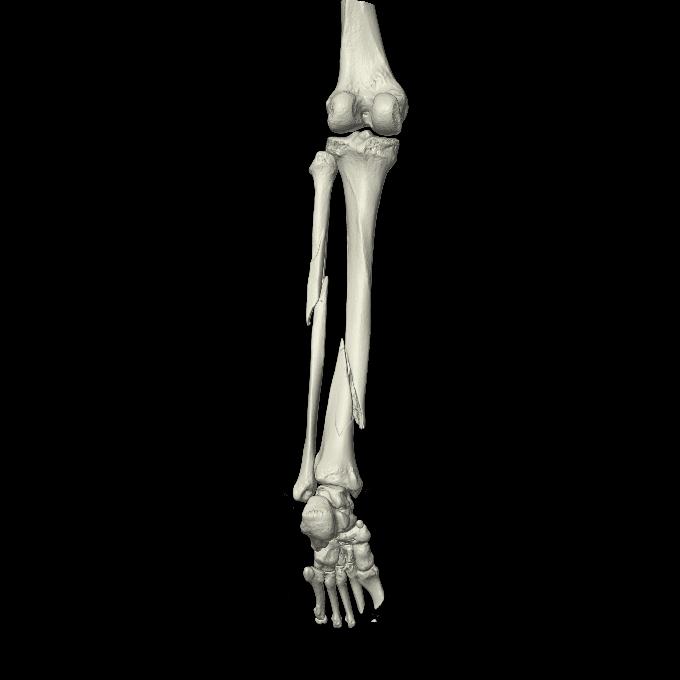

102755 1/4 2R 1/15 2R 右足関節 68歳女性 右三果脱臼骨折